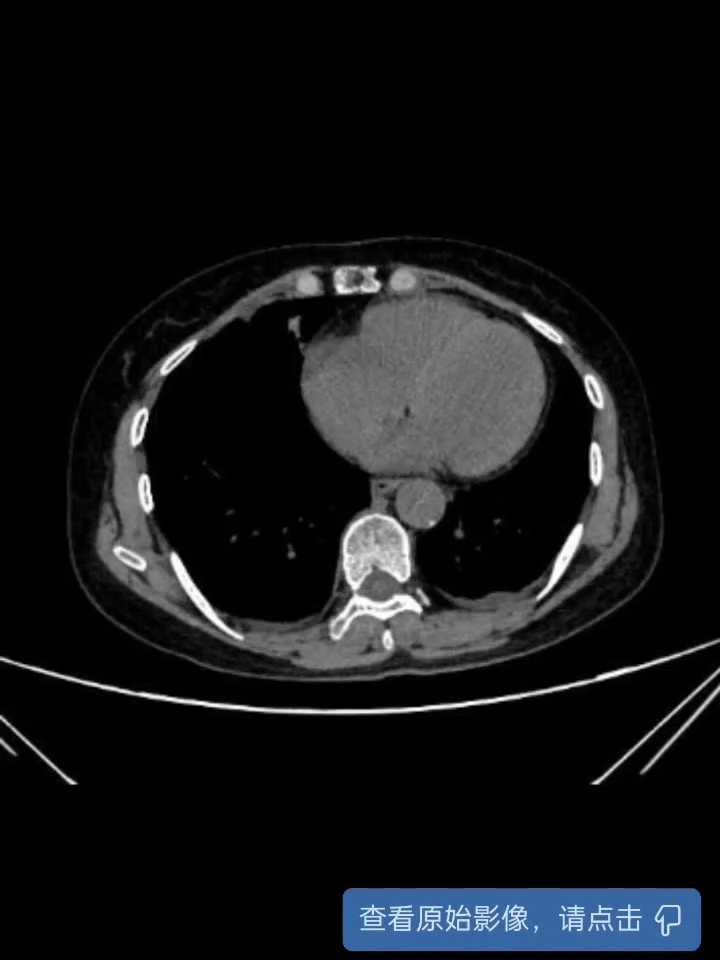

术后腹部CT: